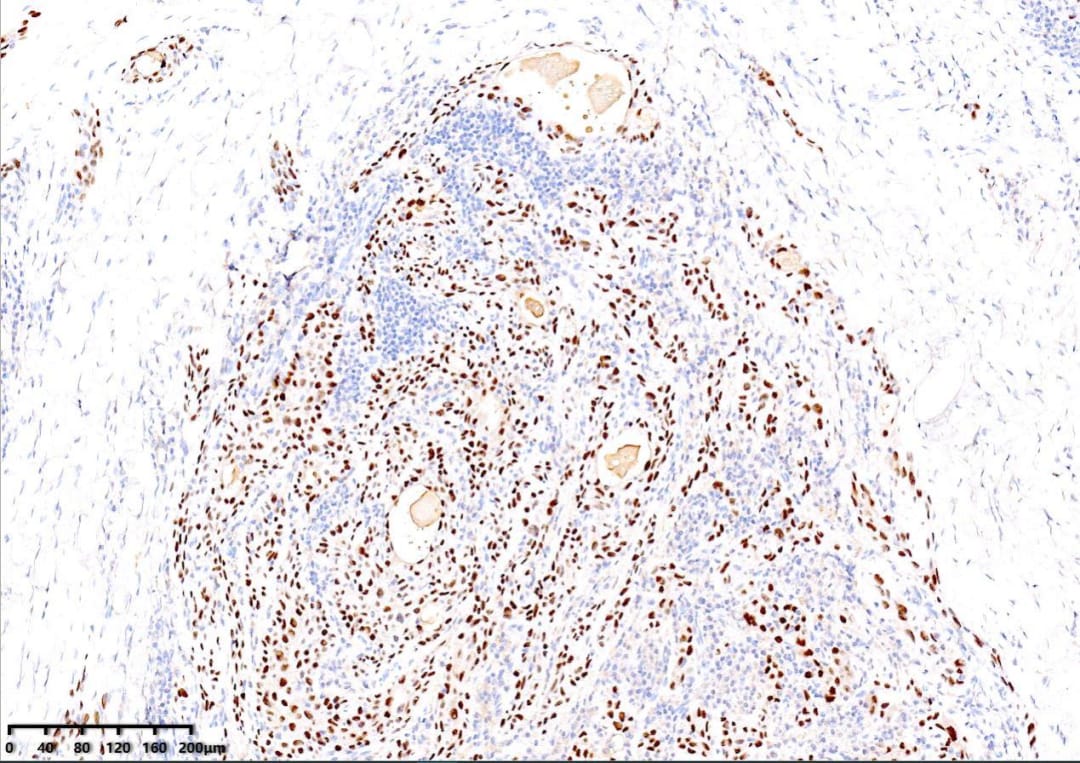

P63(+)

PAX8(+)

TTF-1(+)

免疫组化结果显示:CK19(+)、p40(+)、p63(+)、PAX8(+)、TTF-1(+)、CK5/6(+)、CyclinD1(+)。值得注意的是,BRAF V600E(部分+)和p53突变型阳性,Ki67阳性指数约15%。这些分子标记物对于确诊和鉴别诊断至关重要。